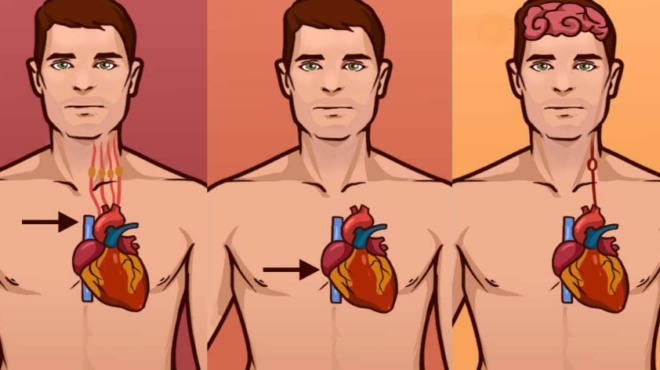

Σημάδια νευρολογικής βλάβης – Συμβουλές για την υγεία: Πολλοί άνθρωποι μπορεί να πάσχουν από νευρολογική διαταραχή και να μην το έχουν αντιληφθεί οι ίδιοι ή οι γύρω τους. Ωστόσο, για την εύρεση νευρολογικής διαταραχής, υπάρχουν οκτώ σημάδια, τα οποία τη φανερώνουν.

Σημάδια νευρολογικής βλάβης – Συμβουλές για την υγεία: Οκτώ συμπτώματα, που δείχνουν πως ίσως πάσχετε από νευρολογική βλάβη

7. Διαταραχές εφίδρωσης: Αποτελούν ένδειξη για πρόβλημα στη μεταφορά σημάτων από τον εγκέφαλο στους ιδρωτοποιούς αδένες.